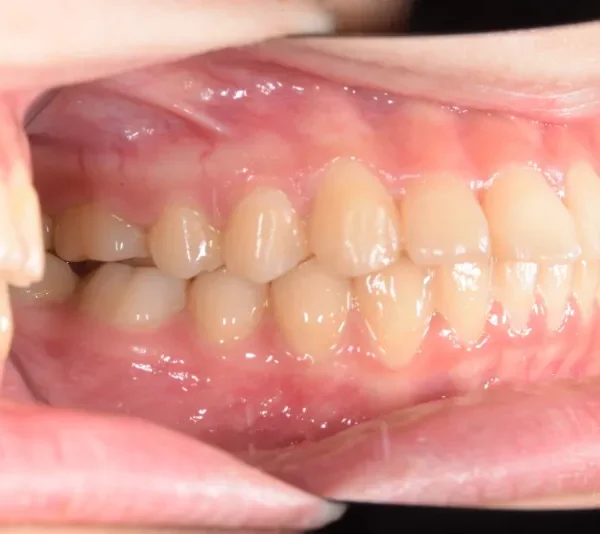

• 治療終了後

治療終了後

乳歯があるうちは上下オリジナル固定装置を利用し、永久歯が生えそろったらマルチブラケット装置を利用して治療しました。

治療回数35回、5年9ヶ月の治療期間で矯正治療を終了しました。